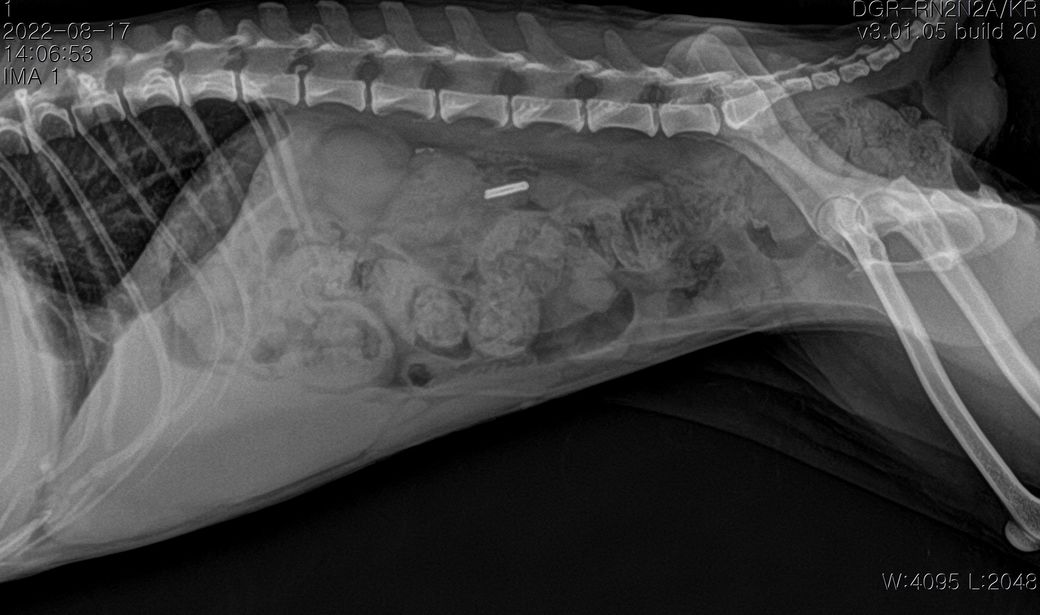

폐에 종양의심소견이 보인다고 해서요.

7월부터 기침을 간헐적으로 하다가 최근 심해져서 병원에 갔는데 엑스레이 상 폐종양이 의심된다고 해서요.

첨부해주신 사진만을 기초로 볼때 폐종양인 경우 좌측 폐전엽부의 종양이, 폐종양이 아닌 경우 종격동내의 종양 특히 흉선종양의 가능성이 높아 보입니다.

이 두가지 종양의 가능성이 사실 가장 높은 상태에서 CT 촬영을 해보아야 하는 이유는

폐종양의 경우 수술로 적출하는것이 비교적 수월하고 수술 이후 어느 정도 절제 하느냐에 따라 정상 생활까지 가능한 상태가 될 수 있기 때문입니다.

물론 폐 종양이 좌측 폐 전엽의 앞쪽 부분에 국한하여 있을 때만을 이야기 하는것으로

만약 좌측 폐전엽의 뒤쪽 부분까지 적출해야 하는 상태의 종양인 경우 수술 이후 호흡 부전이 잘 오고 산소처치를 계속 받으면서 살아야 할 가능성도 고려해야 합니다.

좌측 폐는 산소 교환 능력의 40% 정도를 차지하고 폐엽 절제술 후 산소 교환능에 영향을 주는 기준점이 40% 폐엽이니까요.

또한 흉선종인 경우 이정도 크기로 증가하는 경우에는 대부분 adenocarcinoma인 경우가 많고 그런 양상인 경우 혈관이나 미주신경 침습등의 가능성이 높아 수술불가 판정이 나올 수 있습니다.

앞으로의 처치 방향을 결정하기 위해서라도 CT 촬영을 통해 수술 가능종양인지, 수술을 하지 않더라도 다른 중재적 시술이나 내과적 치료의 플랜을 짜야 하는 상황이라고 보시면됩니다.

현재 위치가 그리 좋지 않은 상태이기 때문에 기대 수명을 말하라면 어렵지만

지금 당장 뇌출혈로 사망해도 이상할게 없는 상태이나 진단과 치료 방향에 따라 훨씬 오랜 기간 생존할 가능성이 있으니 주치의와 잘 상의해 보시는걸 권합니다.